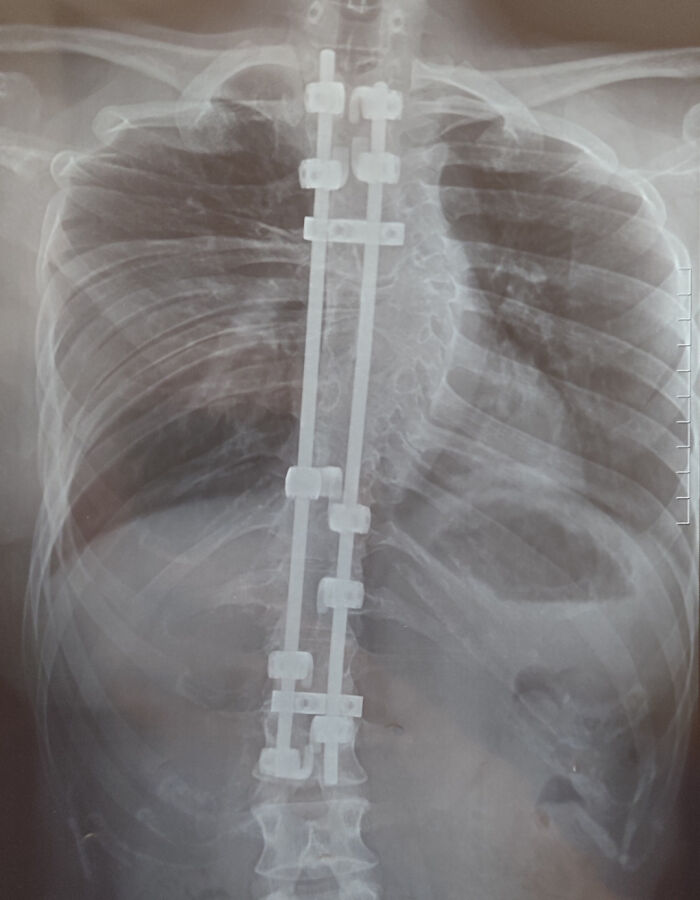

I Have Forked Ribs On My Right Side

A relative had this surgery, so maybe it's because it's an older person but there are moves she is not allowed to do anymore. Bend forward without support for instance. But her back is straight now, which is a game changer.